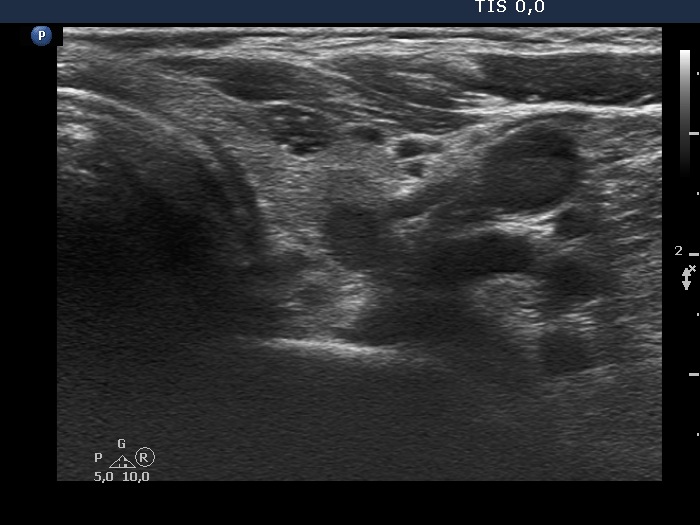

Ultrasonography. The thyroid was echonormal. There were several nodules in the left lobe. The largest in the upper pole presented all but one of the possible suspicious characteristics, it was deeply hypoechoic, had irregular margins, a microcalcification and showed abutting and bulging contours. Moreover, the intranodular vascularization was irregularly increased. One of the other lesions presented back wall figures while the third one showed taller-than-wide shape.